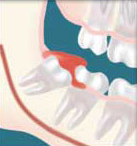

Partial Bony Impactions: There is enough space to allow the wisdom tooth to only partially erupt. It cannot function in the chewing process and creates cleaning problems.

Infection - Without enough room for total eruption, the gum tissue around the wisdom tooth can become irritated and infected, resulting in recurrent pain, swelling and problems with chewing and swallowing.

Damage - If there is inadequate room to clean around the wisdom tooth, the tooth directly in front, the Second Molar, can be adversely affected resulting in gum disease (bone loss) or cavities ( more appropriately known as dental caries or decay).